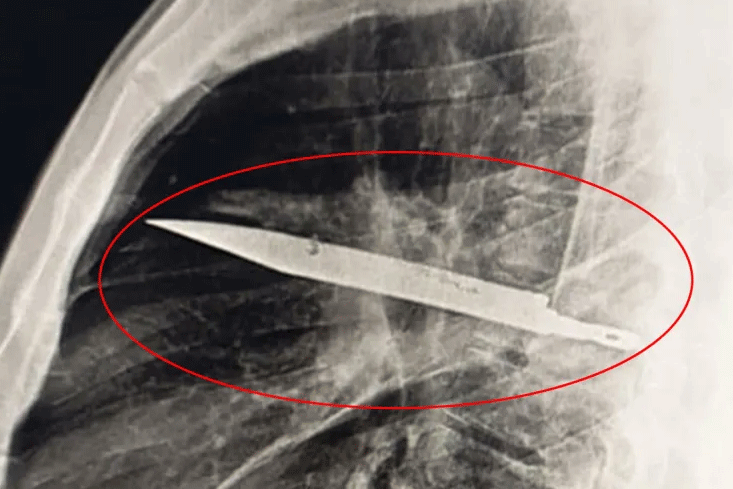

Điện tâm đồ ghi nhận tim của bà Sam xuất hiện hiện tượng ngoại tâm thu - một dạng loạn nhịp tim. Tình trạng này thường vô hại nhưng đôi khi có thể nguy hiểm. Nữ bệnh nhân làm thêm xét nghiệm máu và chụp CT vì từng bị chấn thương đầu.

Kết quả gây sốc: Bà Sam có một khối u não. “Đầu tôi quay cuồng. Tôi gọi cho chị gái trong hoảng loạn và buộc phải đối diện với sự hữu hạn của chính mình. Tôi ngủ trong tư thế ngồi, sợ sẽ không tỉnh dậy”, bà Sam nhớ lại.

Vì vị trí khối u, bác sĩ không thể phẫu thuật. Dù nhiều khả năng lành tính, u có thể ảnh hưởng đến thị lực, giọng nói và gây co giật. Sam phải uống thuốc hằng ngày, chụp MRI não hằng tháng. Năm 2022, bà còn trải qua thủ thuật điều trị loạn nhịp tim.